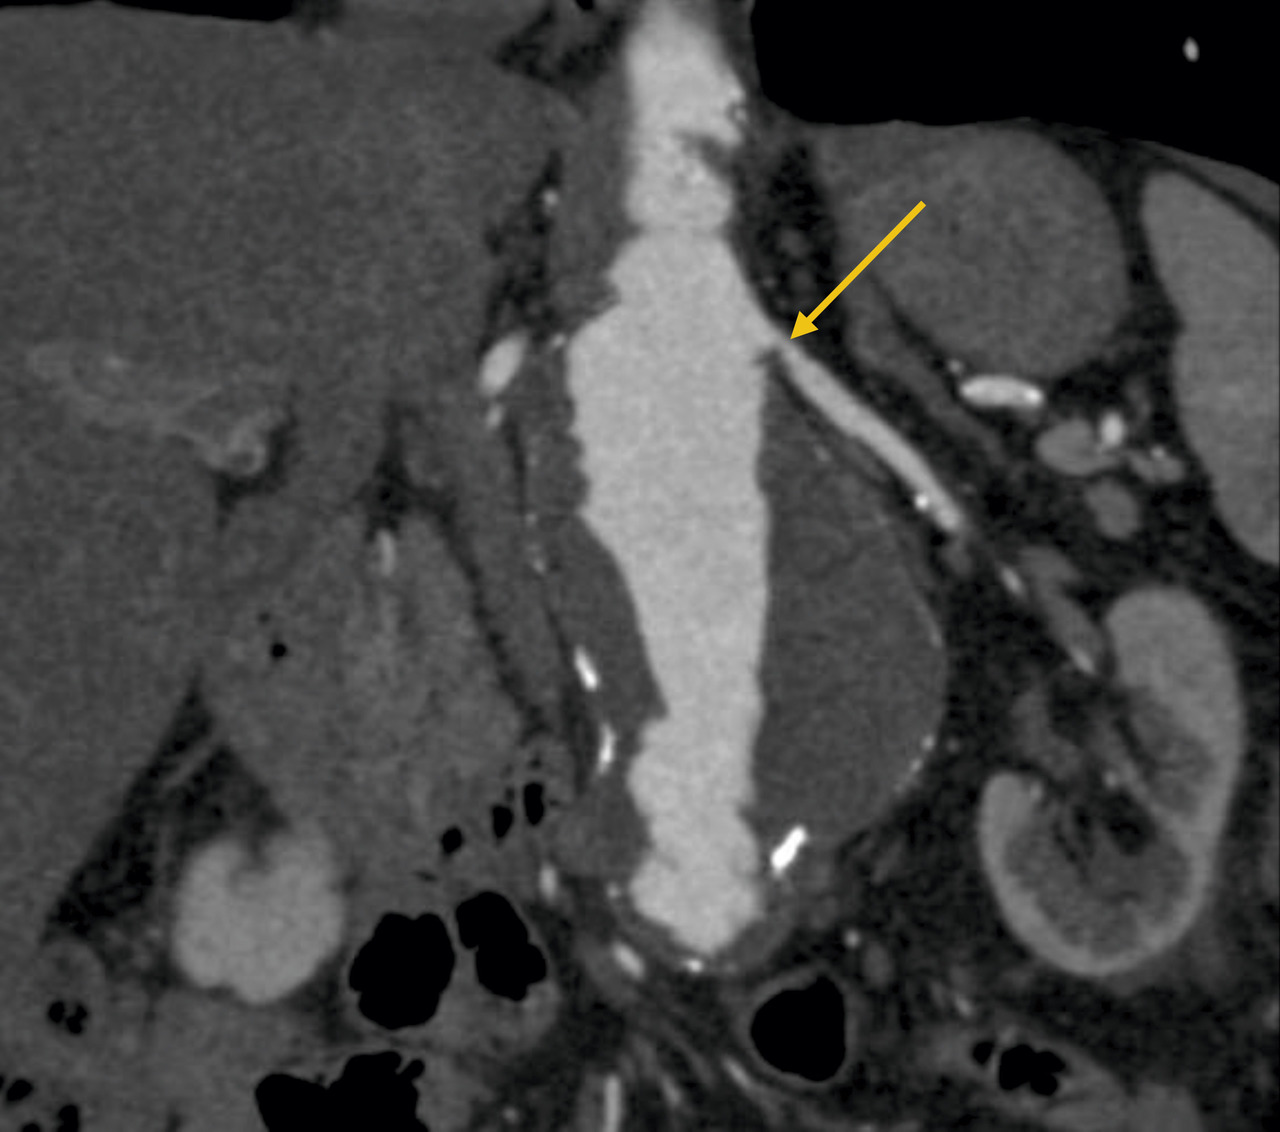

L’échographie-Doppler, l’angio-tomodensitométrie (angio-TDM [fig. 2] et l’angio-imagerie par résonance magnétique (angio-IRM) [fig. 3] permettent le diagnostic de sténose de l'artère rénale. Ils estiment à la fois le degré de sténose (exprimé en pourcentage de réduction du diamètre) et l’impact sur la vascularisation d’aval. Ces 3 examens sont validés et recommandés en première intention. Leur utilisation dépend de l’accessibilité et des habitudes locales. Il est à noter que l’écho-Doppler, très sensible et spécifique dans la sténose de l'artère rénale athéromateuse sous réserve d’un opérateur entraîné, est de sensibilité imparfaite dans la fibrodysplasie, dans laquelle l’angio-TDM est l’examen de référence.

Le tableau résume les avantages et inconvénients respectifs des 3 examens de référence. L’artériographie est réservée aux revascularisations (fig. 4), et n’a pas de place à titre diagnostique.

Dans la sténose de l'artère rénale athéromateuse, on retrouve une plaque habituellement unique, plus une moins calcifiée, ostiale, proximale ou tronculaire, responsable d’une réduction du diamètre endoluminal d’une ou des artères rénales (fig. 2 et 3).